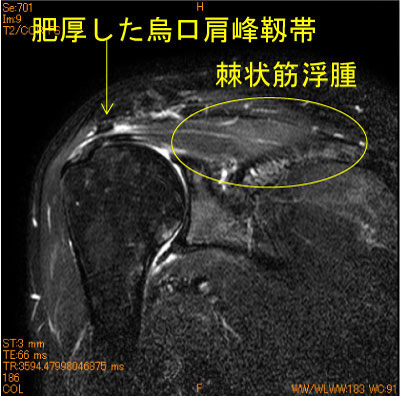

40代女性、バイオリン、ハープ奏者、 肥厚した烏口肩峰靭帯が棘上筋腱と滑液包側を擦っている。

棘上筋筋腹の脂肪抑制T2 high changeは筋浮腫の所見、慣れてくると各靱帯が同定出来る。

筋浮腫という病態がある。脂肪抑制T2WIは不可欠。